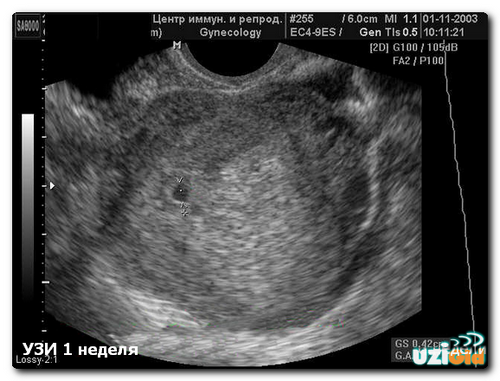

УЗД на 1 тижні вагітності

Фахівці не призначають УЗД під час першого тижня вагітності, так як сам факт зміни положення жінки ще не підтверджений. Жінка навіть не буде здогадуватися про такому маленькому терміні. Про вагітність як про становище говорять вже після 3-го тижня і УЗД може її підтвердити починаючи з цього терміну.

УЗД на 1-му тижні може проводитися. Тільки приводом для нього буде служити не підтвердження вагітності. УЗД в цей період фахівці призначають в наступних випадках:

- Перевірка порожнини матки на присутність міоми, згустків крові, кісти і т. Д.,

- Дослідження ендометрія,

- Підготовка до стимуляції вагітності,

- Позитивний результат після стимуляції.

УЗД в цей період не покаже вагітність. Показання для УЗД можуть бути тільки суто індивідуальні.